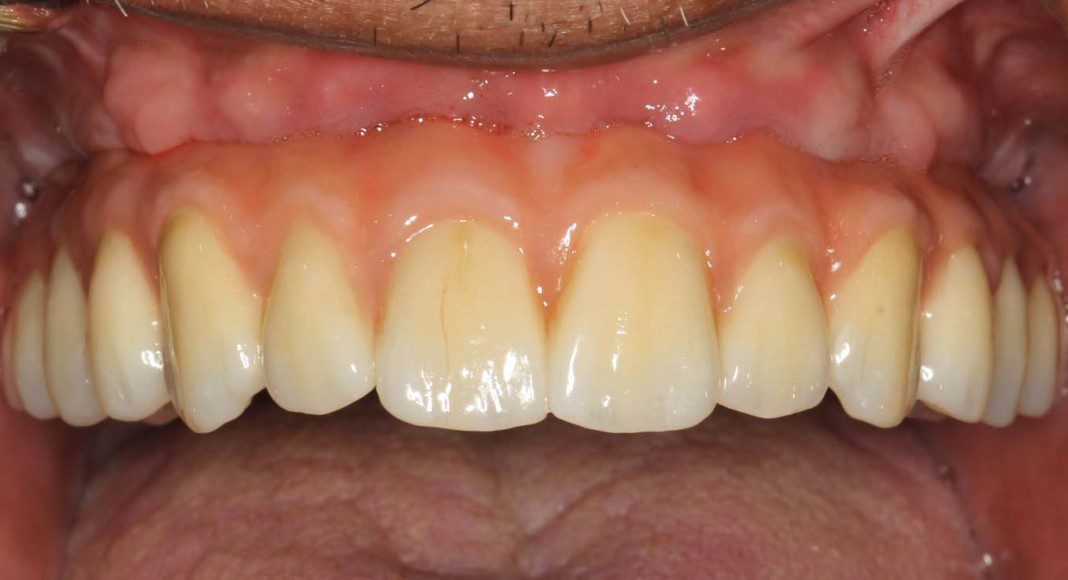

Upper implants are “uncovered” (an incision is made over the implants to separate the tissue that is covering the implants. Whenever possible the incision favors the palatal tissues to bring better quality tissue in front of the implants). Implant impression copings are placed. Frontal view.

Lower implants are “uncovered” (an incision is made over to separate the tissue that is covering the implants. If there is an option to move better tissue from the tongue side of the implants, the incision will be placed on the tongue side of the implants). Implant impression copings are placed. Frontal view.